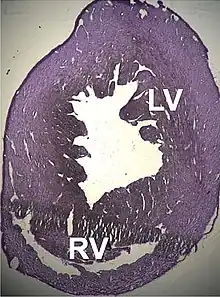

In heart muscle

The ACTC1 gene codes for the α-actin isoform present in heart muscle. It was first sequenced by Hamada and co-workers in 1982, when it was found that it is interrupted by five introns.[150] It was the first of the six genes where alleles were found that were implicated in pathological processes.[151]

A number of structural disorders associated with point mutations of this gene have been described that cause malfunctioning of the heart, such as Type 1R dilated cardiomyopathy and Type 11 hypertrophic cardiomyopathy. Certain defects of the atrial septum have been described recently that could also be related to these mutations.[153][154]

Two cases of dilated cardiomyopathy have been studied involving a substitution of highly conserved amino acids belonging to the protein domains that bind and intersperse with the Z discs. This has led to the theory that the dilation is produced by a defect in the transmission of contractile force in the myocytes.[155][151]

The mutations in ACTC1 are responsible for at least 5% of hypertrophic cardiomyopathies.[156] The existence of a number of point mutations have also been found:[157]

Pathogenesis appears to involve a compensatory mechanism: the mutated proteins act like toxins with a dominant effect, decreasing the heart's ability to contract causing abnormal mechanical behaviour such that the hypertrophy, that is usually delayed, is a consequence of the cardiac muscle's normal response to stress.[158]

Recent studies have discovered ACTC1 mutations that are implicated in two other pathological processes: Infantile idiopathic restrictive cardiomyopathy,[159] and noncompaction of the left ventricular myocardium.[160]